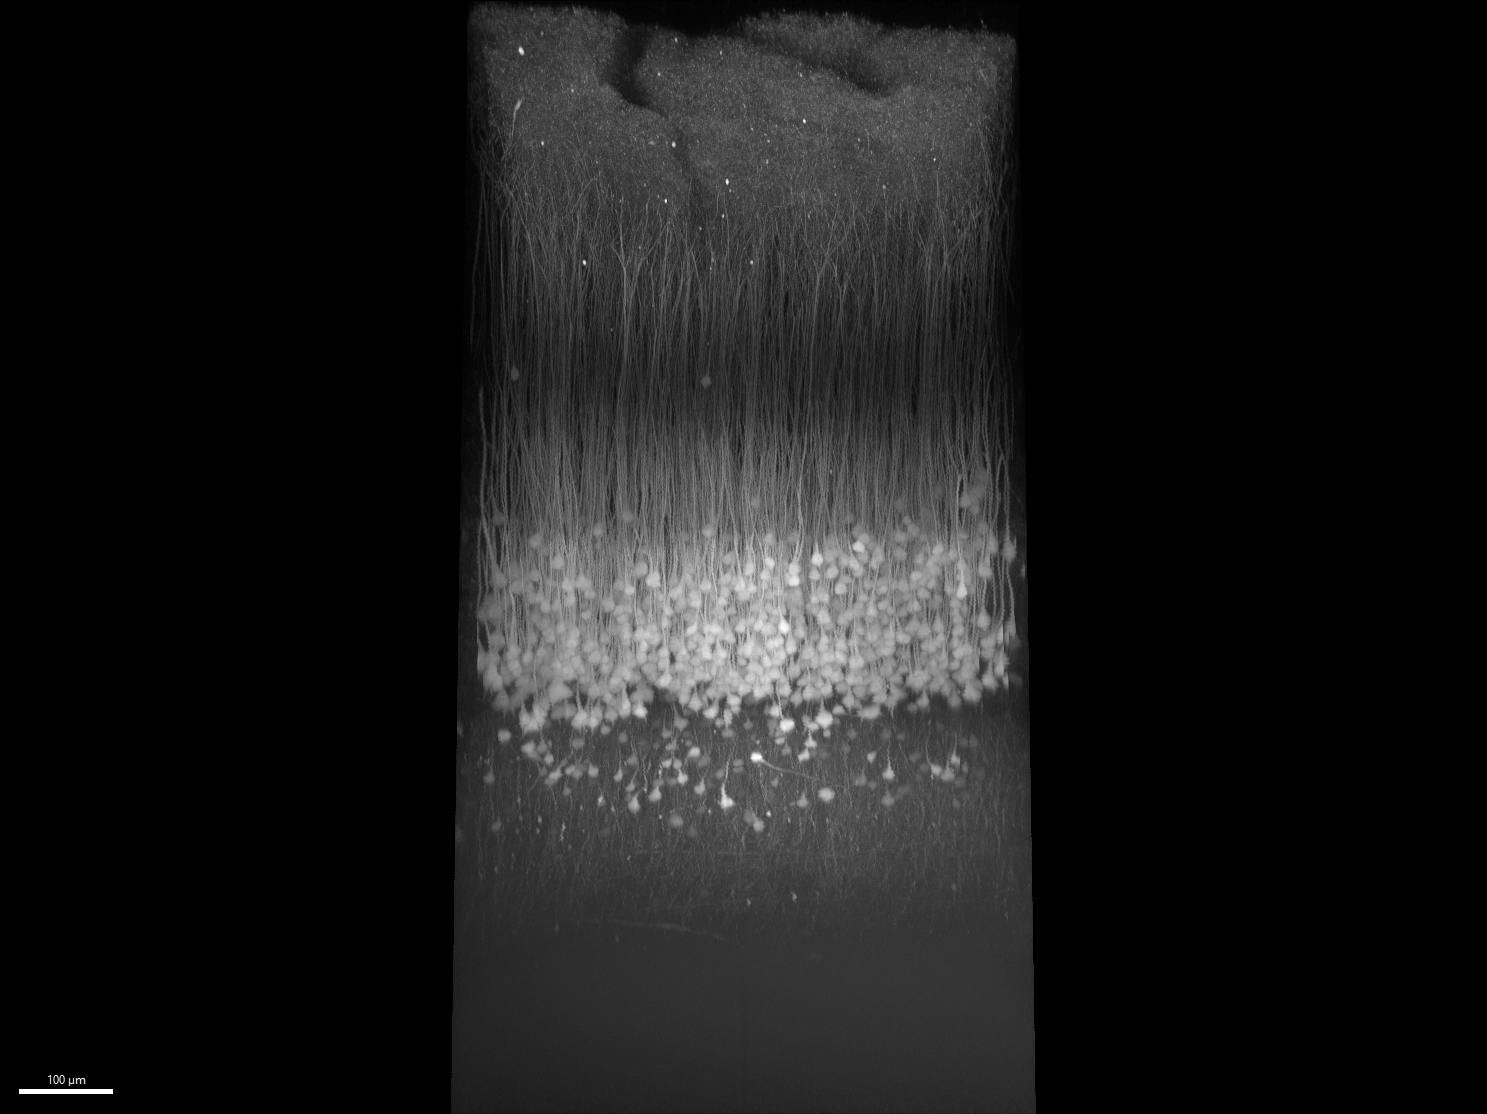

If two or more photons excite a fluorophore at the same time, it is excited with the same energy as a single photon and emits corresponding fluorescence. Even though the system uses NIR lasers, which have a longer wavelength than visible light, the light emitted is within the shorter wavelength visible spectrum. For example, green fluorescent protein (GFP) can be excited at 920 nm, but emits fluorescence around 500 nm. The multiphoton absorption of the fluorophore described above only happens in high-density photon areas, which correspond to the microscope’s objective focus spot. Therefore, the MPE image has optical sectioning and good contrast at various resolutions and allows researchers to observe events within living animals 1 mm+ beneath the sample surface (see Fig. 1).